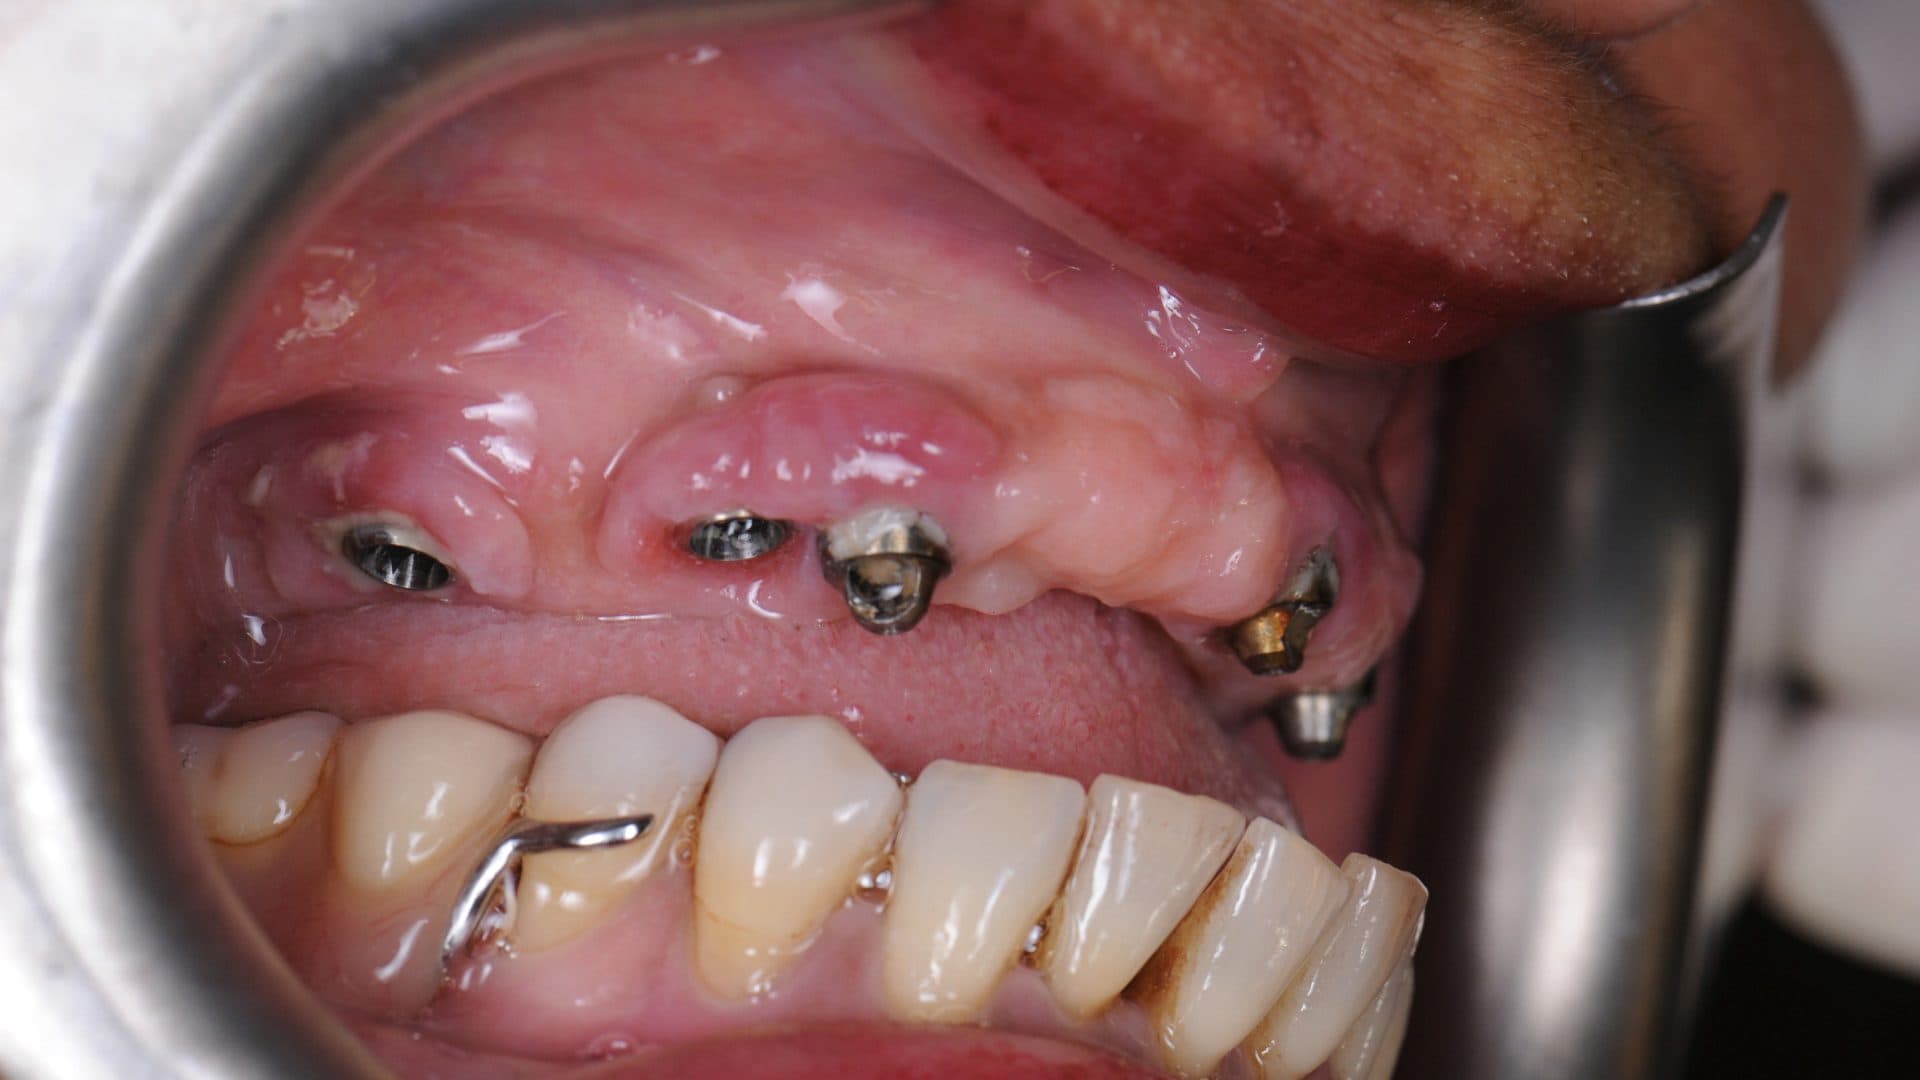

The implants in the picture below were also clean at one time, and probably looked great before the wear and tear, but click through on the picture to see the damage done when implants are placed incorrectly, causing the teeth to be bulky and impossible to clean.

Examples Of Poor Standards